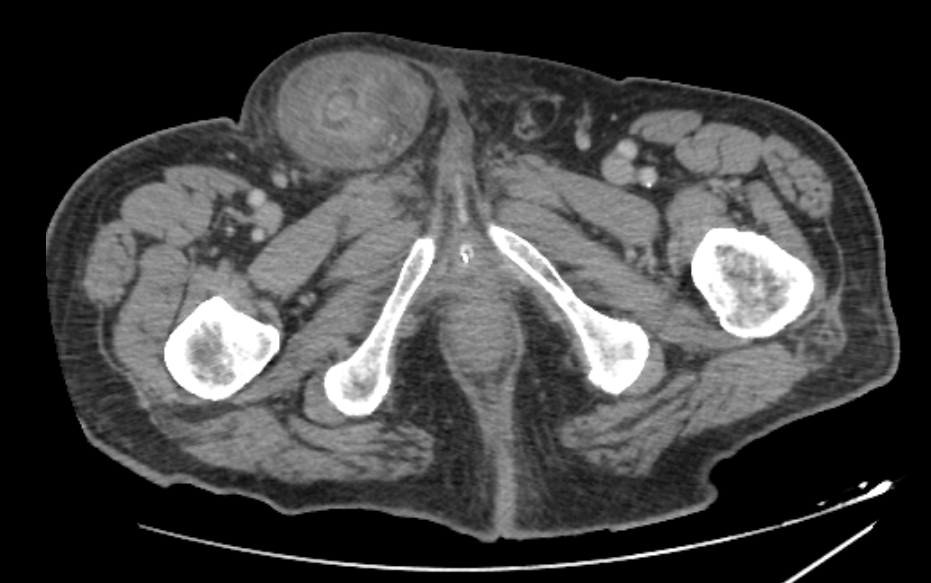

On admission, his vital signs were stable: blood pressure was 125/85 mmHg, pulse rate was 80 bpm and body temperature was 37°C. Physical examination revealed a painful, tender and irreducible right inguinal hernia without signs of peritonitis on abdominal palpation. Laboratory tests showed an elevated C-reactive protein (CRP 112.6 mg/L) as the only abnormal finding, with white blood cell (WBC) count at 2,240/µL and neutrophil percentage at 58.1%. An abdominal CT scan revealed caecal protrusion within the inguinal hernia sac, hyperaemia of the colonic wall, free fluid in the hernia sac and ascites in the peritoneal recesses (figure 1 – 3).

Figure 3: CT Scan

Figure 3